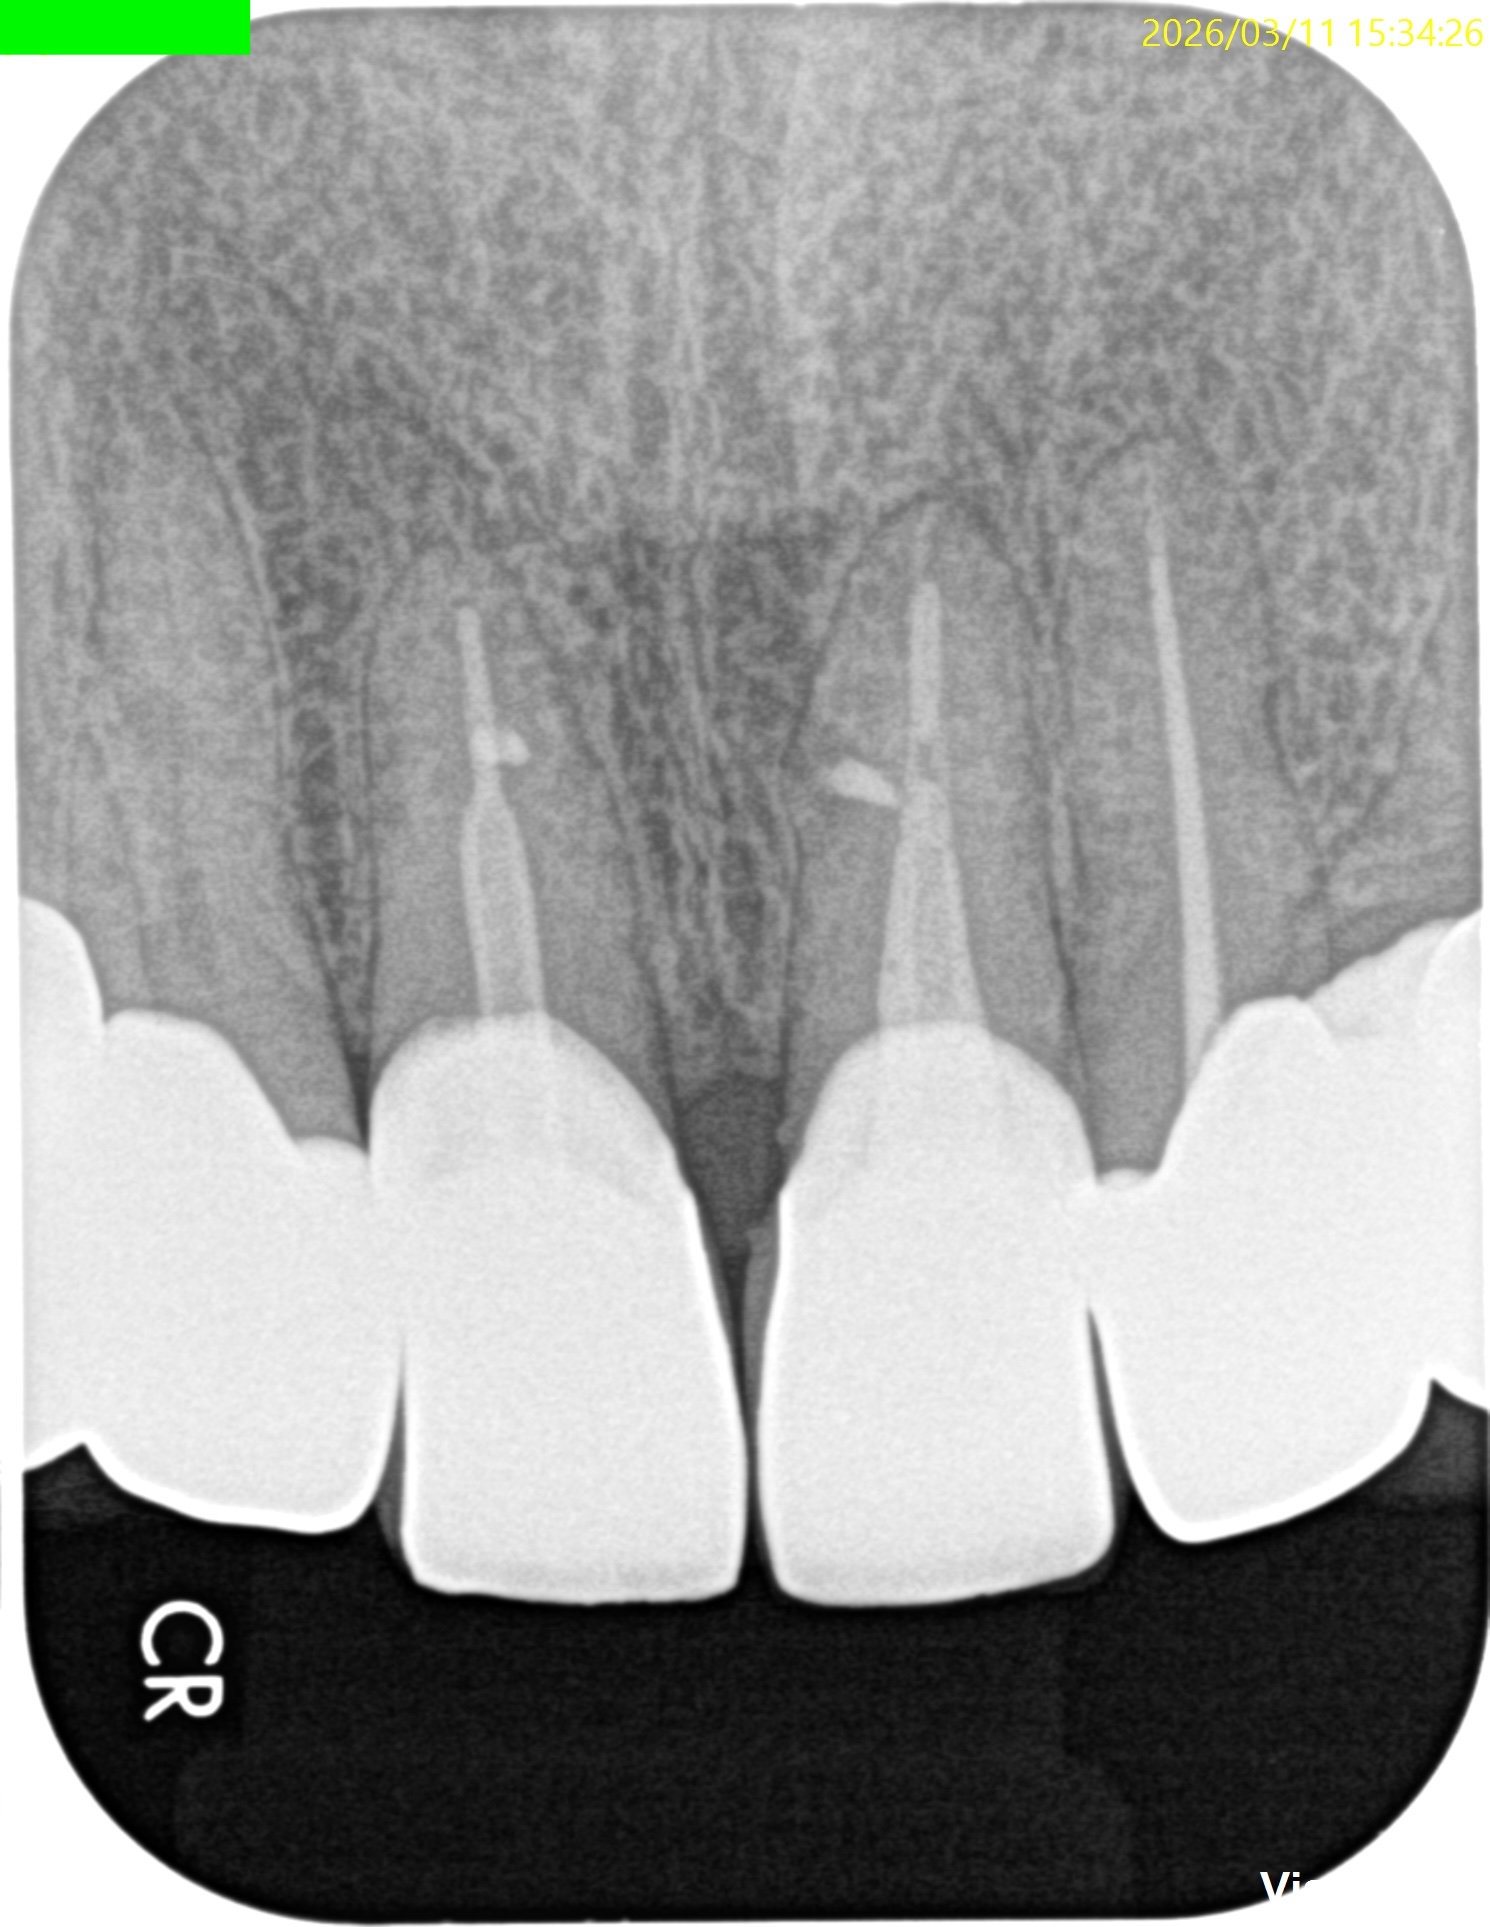

#8,9 Microsurgery 1yr recall(2026.3.11)

#9

初診時と比較した。

問題は大きく解決されている。

初診時のSinus tract, 臨床症状は消失した。